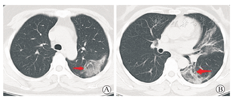

入院后予磷酸奥司他韦胶囊(75 mg/次,2次/d)抗流感病毒,莫西沙星片(0.4g/次,1次/d)抗感染及相关祛痰止咳等对症治疗。患者仍有反复发热,体温为37.3~38.9 ℃。因患者存在新型冠状病毒肺炎(COVID-19)流行病学史,于1月22日送检咽拭子及血清,经金华市及浙江省疾病预防控制中心检测,确认2019-nCoV核酸阳性,确诊为COVID-19。加用干扰素α-2b针雾化吸入(500万U,2次/d);洛匹那韦/利托那韦片(2片/次,1次/12 h)口服;同时予中药辅助治疗,体温恢复正常。1月28日患者再次出现发热,体温最高37.8 ℃,无明显咳嗽、咳痰,无胸闷气急,无气喘。复查床边胸片提示左肺感染,较1月21日病灶进展。复查血常规:白细胞7.8×109/L,嗜中性粒细胞占比0.796,淋巴细胞占比0.132,超敏CRP 20.8 mg/L;血降钙素原0.041 ng/mL;复查咽拭子2019-nCoV核酸阳性;予上述药物继续抗病毒及抗感染,加用甲泼尼龙琥珀酸钠针(40 mg,1次/d)静脉滴注,共用3 d。1月29日,患者体温恢复正常,无咳嗽、咳痰,无胸闷气喘,自觉症状较前好转,食欲好转。1月30日停用甲泼尼龙琥珀酸钠针,其他治疗同前。1月31日,患者体温持续正常,无明显不适。复查胸部CT,示左肺及右肺下叶片状高密度影,边缘模糊,右肺下叶膨胀不全(图2)。2月3日,复查胸部CT,炎症范围较1月31日有所吸收(图3)。复查血常规:白细胞6.74×109/L,嗜中性粒细胞占比0.76,淋巴细胞占比0.165,超敏CRP 1.0 mg/L,血降钙素原0.04 ng/mL。2月3日和4日复查咽拭子2019-nCoV核酸,检测均阴性,达到出院标准,予2月5日出院。

注:箭头所标注为新增病灶